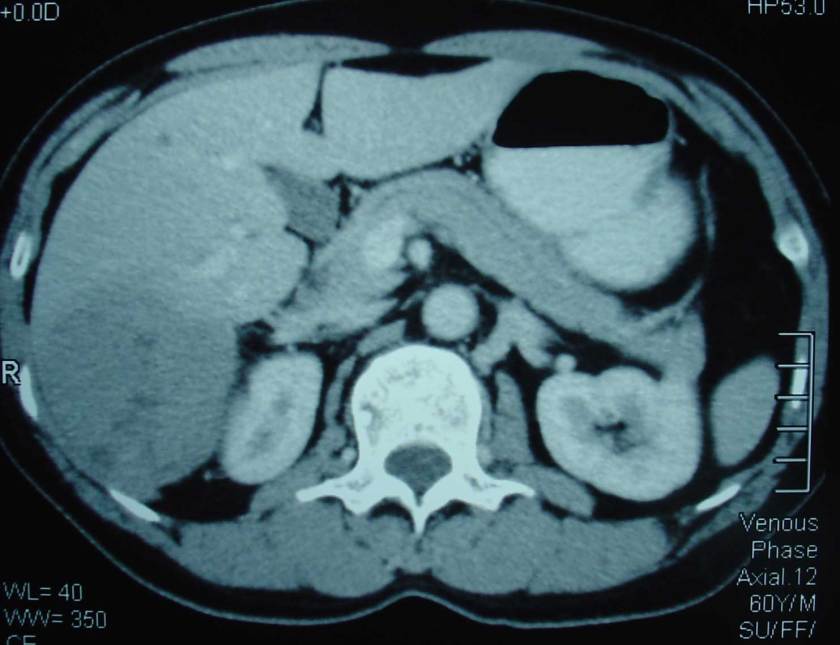

Pang (H5) adalah seorang pria berusia 61 tahun. Beberapa waktu pada bulan Februari 2008, ia mengalami rasa nyeri pada abdomen. Hasil ultrasonography menunjukan ada massa bulat berbatas tegal berukuran 5.2 x 5.3 x 6.5 cm pada lobus kanan heparnya (Segmen 6).

Pang dirujuk ke spesialis bedah di rumah sakit swasta. Hasil CT-scan menunjukan hepatoma lobus kanan dengan ukuran 8 x 7 x 8 cm pada segmen 6 dan 7. Pang menjalani operasi reseksi tumor pada 25 Maret 2008. Operasi ini menghabiskan biaya 20.000 RM.

Pang menjalani terapi ini dari September 2008 sampai Februari 2009 dan melakukan total 5 sesi. Tapi hasilnya mengecewakan. Hasil CT-Scan menunjukkan metastasis ke paru-paru. Jumlahnya ada 5 nodul pada paru-paru kiri dan kanan. Ukurannya berdiameter sekitar 6 sampai 12 mm masing-masing. Hasil CT-Scan juga menunjukkan 2 partially nekrotik tumor pada Segmen 7/8 dari livernya. Ukurannya berdiameter kira-kira 4,5 x 6 cm dan 3,5 x 3,5 cm masing-masing.